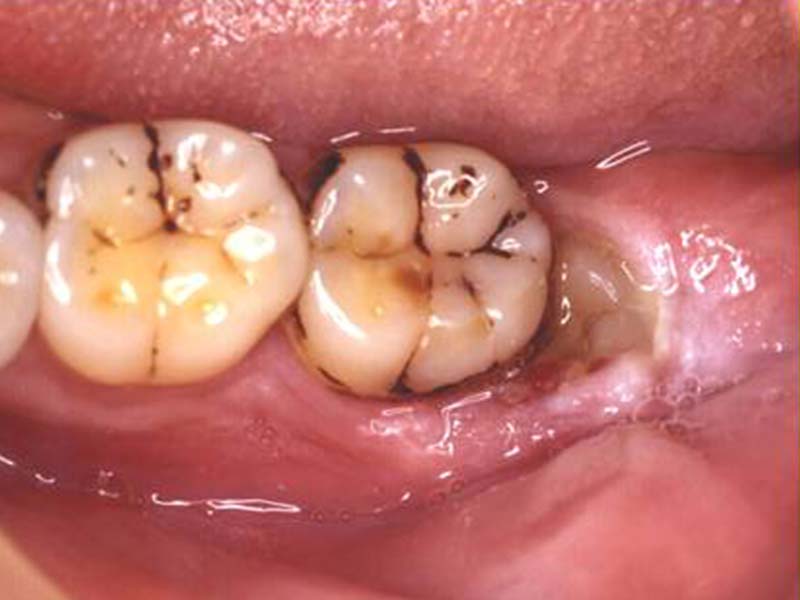

智齒手術

• 智齒手術